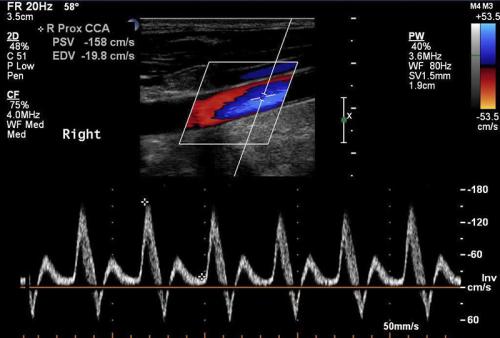

Üriner Sistem Doppler İncelemeler

Doppler USG ürolojide en sık erektil Disfonksiyon (ereksiyon olamama, penis sertleşmesi sorunları, impotans) durumunda, nedenin ara...